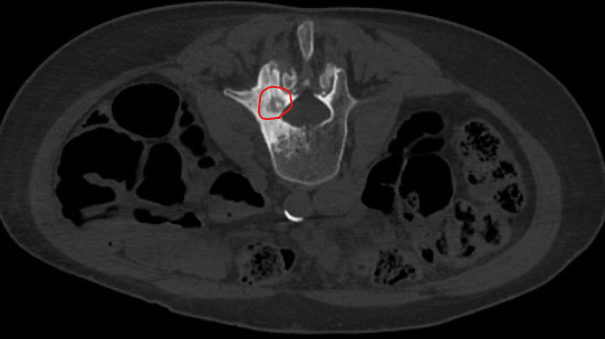

A painful bone lesion known as an osteoid osteoma is seen here in a lumbar vertebra. Note the close location to the spinal canal.

MRI guided cryoablation allows easy visualisation of the ice ball (red circle) allowing our team to stop the freeze once the ice neared the nerve roots in the spinal canal (red arrows). This level of precision is not available with any other imaging modality.